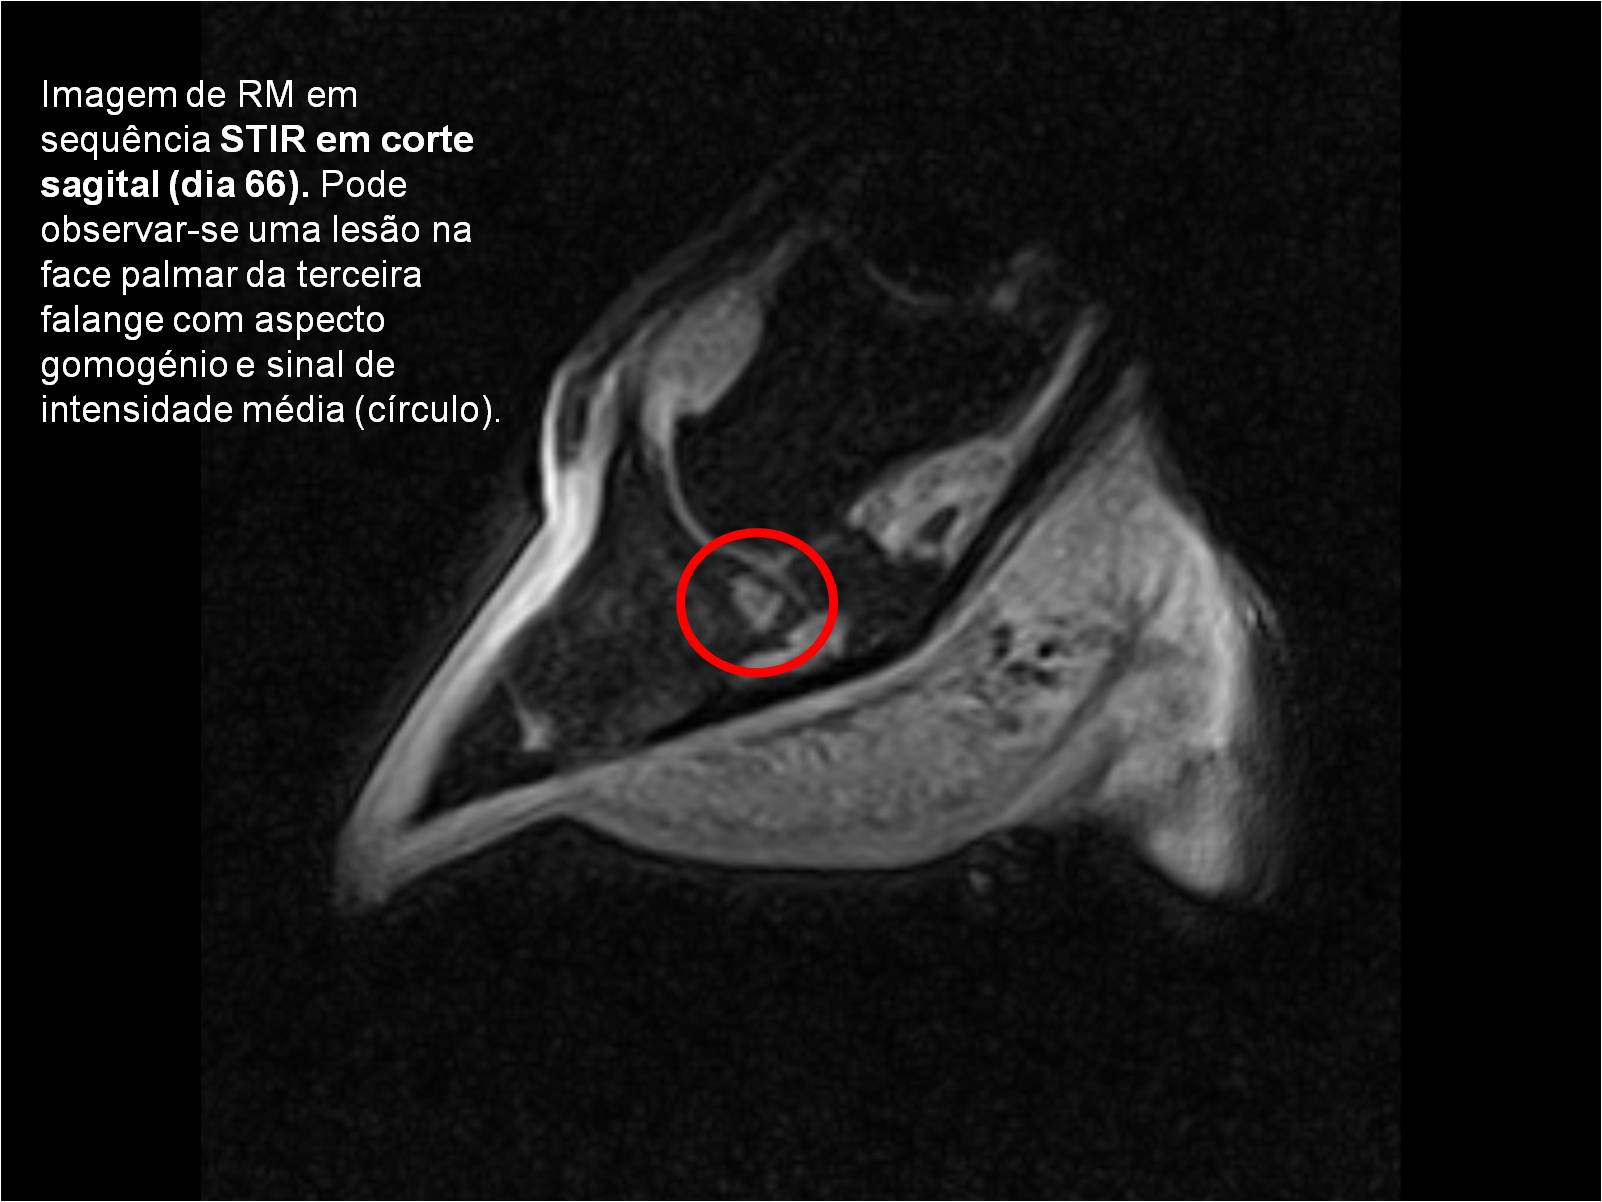

Publisher: Universidade de Évora

Abstract: O relatório de estágio encontra-se estruturado em três partes distintas. A primeira parte faz a caracterização das infraestruturas e funcionamento do Hospital Veterinário de Equinos de Lüsche, Oldenburg, Alemanha, assim como a análise casuística dos casos clínicos acompanhados durante os 6 meses de estágio. A segunda parte consiste de uma revisão bibliográfica sobre quistos do osso subcondral em equinos. Por fim, a terceira parte consta da apresentação e discussão de um caso clínico, nomeadamente o diagnóstico e acompanhamento imagiológico, por ressonância magnética, de um quisto subcondral na terceira falange num cavalo adulto; ### Abstract Equine Practice- Subcondral bone cyst of the third phalanx This internship report is divided in three parts. The first part characterizes the infrastructure and function of the Equine Hospital Lüsche, Oldenburg, Germany, as well as the casuistic of the clinical cases accompanied during the 6 month internship. The second part consists in a bibliographic review of cystic lesions of the subchondral bone in equines. The third part consists in a case report, the diagnostic and imagiological accompaniment, by use of magnetic resonance imaging, of a subchondral bone cyst in the distal phalanx of an adult equine.